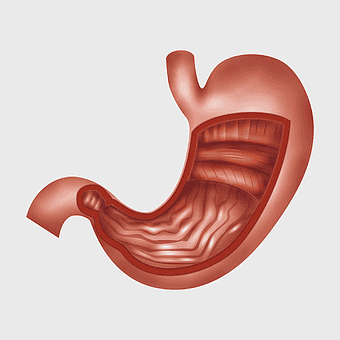

human stomach anatomy, gastrointestinal tract illustration, digestive system organ, abdominal cavity viscus, internal organ diagram, medical biology graphic, human body internal structure -

stomach illustration, full stomach anatomy, abdominal organ depiction, human digestive system, gastroenterology graphics, medical illustration artwork, digestive health visual -